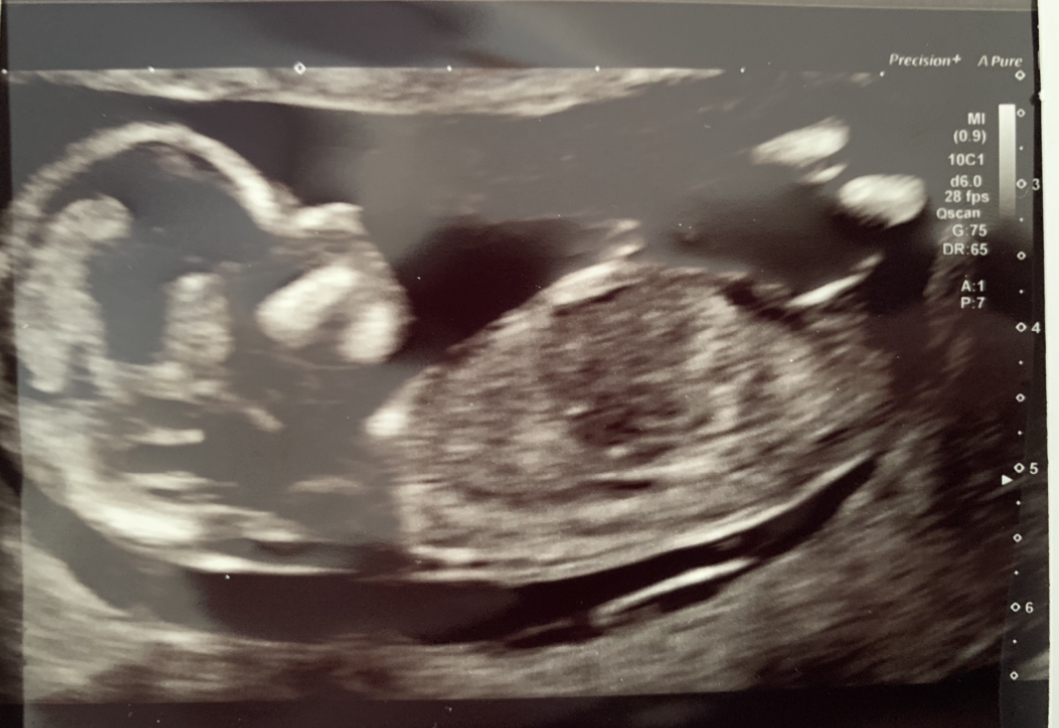

Hey, any guesses boy or girl? 12 weeks 6 days here

Tentative pink lean based on the top pic. In the bottom one I'm not sure what I'm seeing, I feel the nub is not captured and the second picture looks boyish, but that nub in the top one may just not be on the second shot

Boy guess from me. Think There’s stacking on the first photo and the second looks boyish too. Hope you get what you hope for if you have a preference :)

We had our gender scan today and it’s a girl 🥰